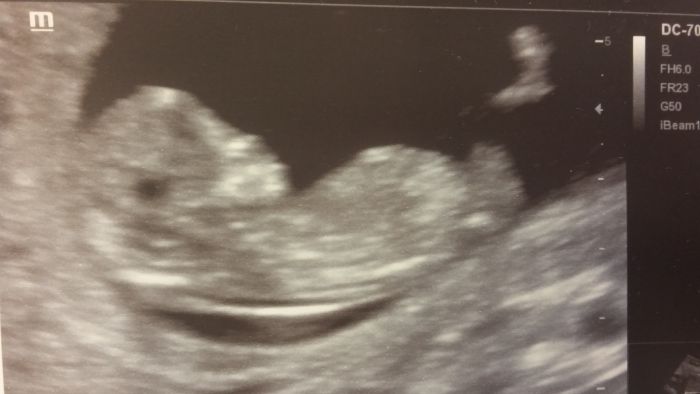

Ahoj holky, nebojte, všem screening dopadne dobře. Já už jen čekám na výsledky z krve, ale na utz jinak všechno v pohodě:) Co se týká oblečení, tak kalhoty jsou mi dost nepohodlný. Jakmile si sednu, tak knoflík tlačí do bříška. Takže já nosím termolegíny a sukně bez zipů a knoflíků. A teď mám dvě nové těhotenské, jen strašně smrdí novotou tak je musím prohnat pračkou:) No a někdo byl zvědavý na fotky, takže se pokusím nahrát toho svýho šesticentimetrovýho obříka.rfotka je z 12+3.

Ten si tam teda lebedí, Kamczo

To teda. A stačilo, aby pan doktor řekl, že ho potřebuje změřit a už se nastavoval a protahoval...:) A asi to bude maratonec, má strašně dlouhý nožičky :-D

Kamco to je krásná fotecka :)